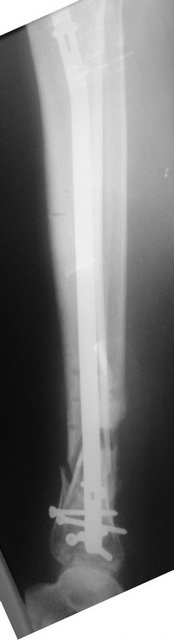

[Ortho] ложный сустав обеих костей правой голени

Имя     : r_postop_ap.jpg

Тип     : image/jpeg

Размер  : 19200 байтов

Url     : http://weborto.net:8080/pipermail/ortho/attachments/20110817/d4952754/attachment-0004.jpg